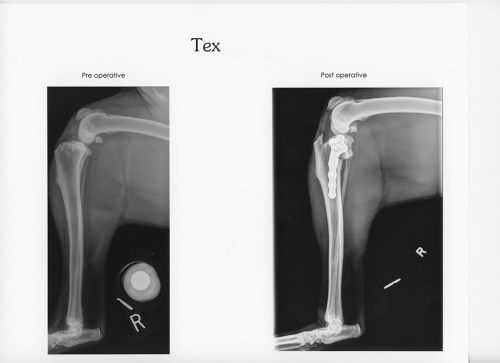

If you follow this blog, then you know that Tex tore the dog equivalent of his ACL back at the beginning of the bird season. The poor dog had to miss October through the middle of December. He recovered well and here are some pictures of his return to hunting fields.

After the TPLO surgery and 12 long weeks of rehab, Tex is as good as new.

It really is amazing surgery. His rear left seems to give him no trouble and he was back to cruising the fields. Then in early January, less than a month after recovery, he blew out his other ACL! The doctor warned that when one goes there is a 50% chance that the same thing will happen to the other knee. So I guess we are just extra lucky. This season is pretty much a total loss for old Tex. The good thing is that he is out of knees to wreck so he should be in tip top shape for next year!

This is what an $8,000 dog looks like.

Next year is going to be awesome, hunting with my bionic dog!